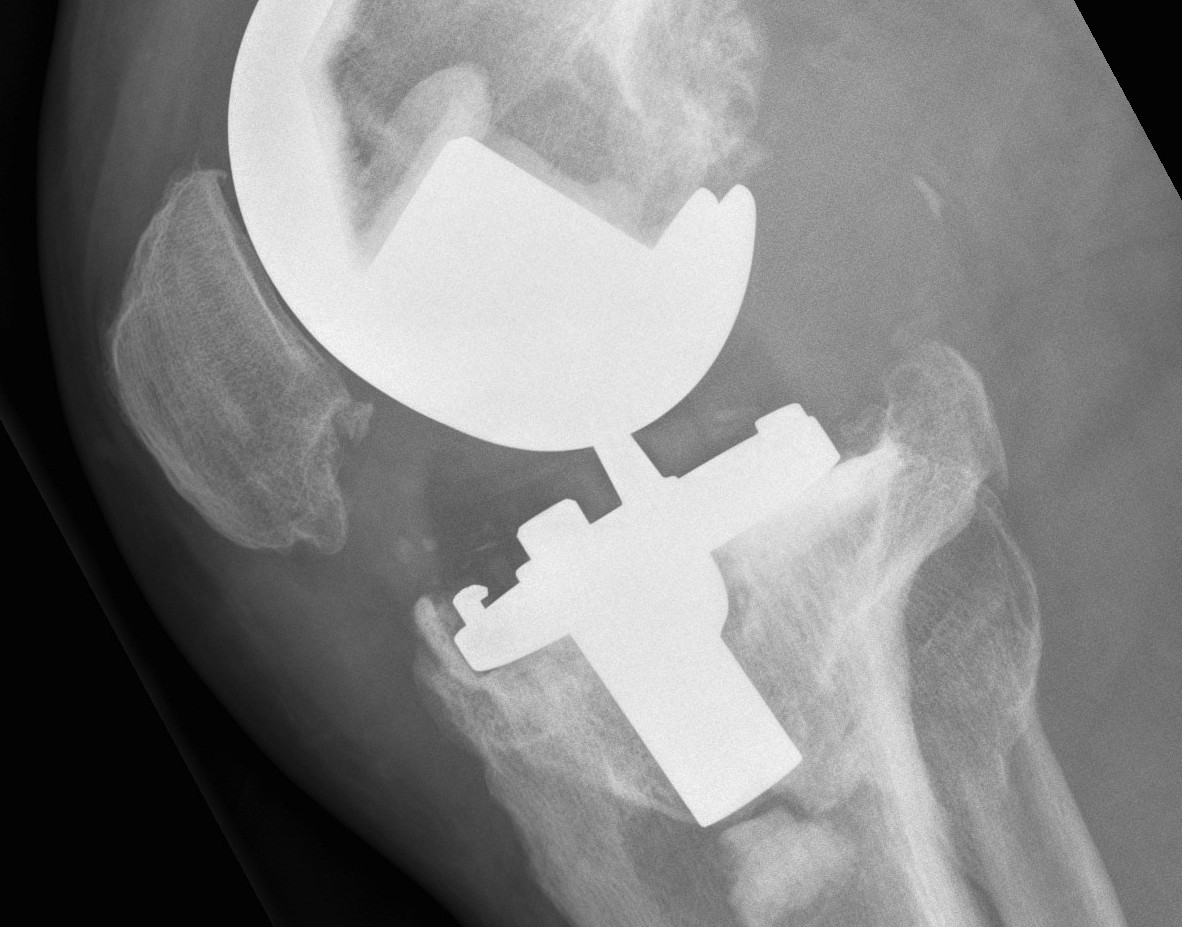

AORI / Andersen Orthopedic Research Institute

T Tibial F Femoral

2. Damaged Metaphyseal

A. One Condyle

2. Damaged Metaphysis

A One condyle

Management

A. Cement < 1cm

B. Augments < 2cm

C. Bone graft